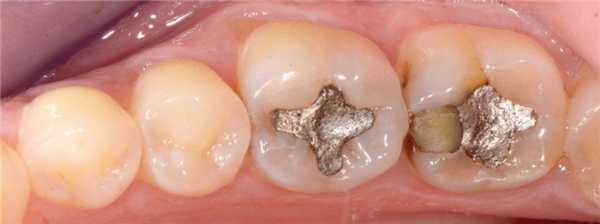

35-летняя пациентка обратилась за стоматологической помощью с просьбой заменить амальгамные реставрации в области первого и второго нижних молярах. Она также сообщала о наличие болезненных ощущений в проекции данных зубов при жевании. В ходе клинического осмотра были идентифицированы реставрации моляров, требующие срочной замены (фото 4). После удаления старых пломб и нанесения универсального адгезива Adhese Universal, объем дентина был восстановлен материалом Tetric EvoFlow Bulk Fill (фото 5). Данный композит обладает очень хорошими свойствами самовыравнивания и автоматически принимает вогнутую форму. В области второго моляра текучий композит вносили одновременно и на окклюзионную и на контактную поверхности. Полимеризацию обеспечивали лампой Bluephase (1200 мВт/см2) в течение 20 секунд. Производитель рекомендует обеспечивать полимеризацию композита на протяжении 10 секунд. Внесенная толщина слоя текучего композита не превышала 4 мм. Благодаря технологии Aessencio опаковость материала значительно увеличивается в процессе полимеризации (фото 5). Эмаль восстанавливали посредством материала Tetric EvoCeram A3, используя технику последовательного наращивания бугров. Фиссуры окрашивали при помощи IPS Empress Direct Color Brown (фото 6). Корректировку окклюзионных соотношений проводили после удаления коффердама. Поскольку бугорки изначально были смоделированы правильно, требовалась лишь минимальная окклюзионная коррекция, после которой приступили к полировке реставрации системой Astropol. Поверхности реставраций плавно сливались с окружающей структурой зуба (фото 7).

Фото 4. Дефектная реставрация в двух нижних молярах.